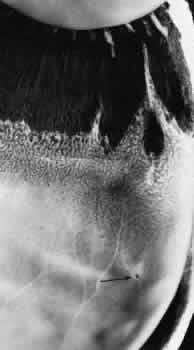

Fig. 12. Enclosed ora bay in a 35-year-old man. Anteriorly, two broad dentate processes converge and join to enclose a bay (island of pars plana). Posteriorly there is a focus of retinal thinning (peripheral retinal excavation; arrow). (× 12.)

PERIPHERAL RETINAL EXCAVATION

Peripheral retinal excavation appears as a rather small oval depression in the retina. Usually this lesion is aligned meridionally with a meridional fold or complex and located 1 to 7.2 mm posterior to the ora serrata (Fig. 13; see Figs. 6 and 12). The focal depression may be surrounded by margins that appear to be elevated; however, microscopic examination reveals that the depression corresponds to afocal loss of the inner retinal layers and that the surrounding tissue is normal (Fig. 14).